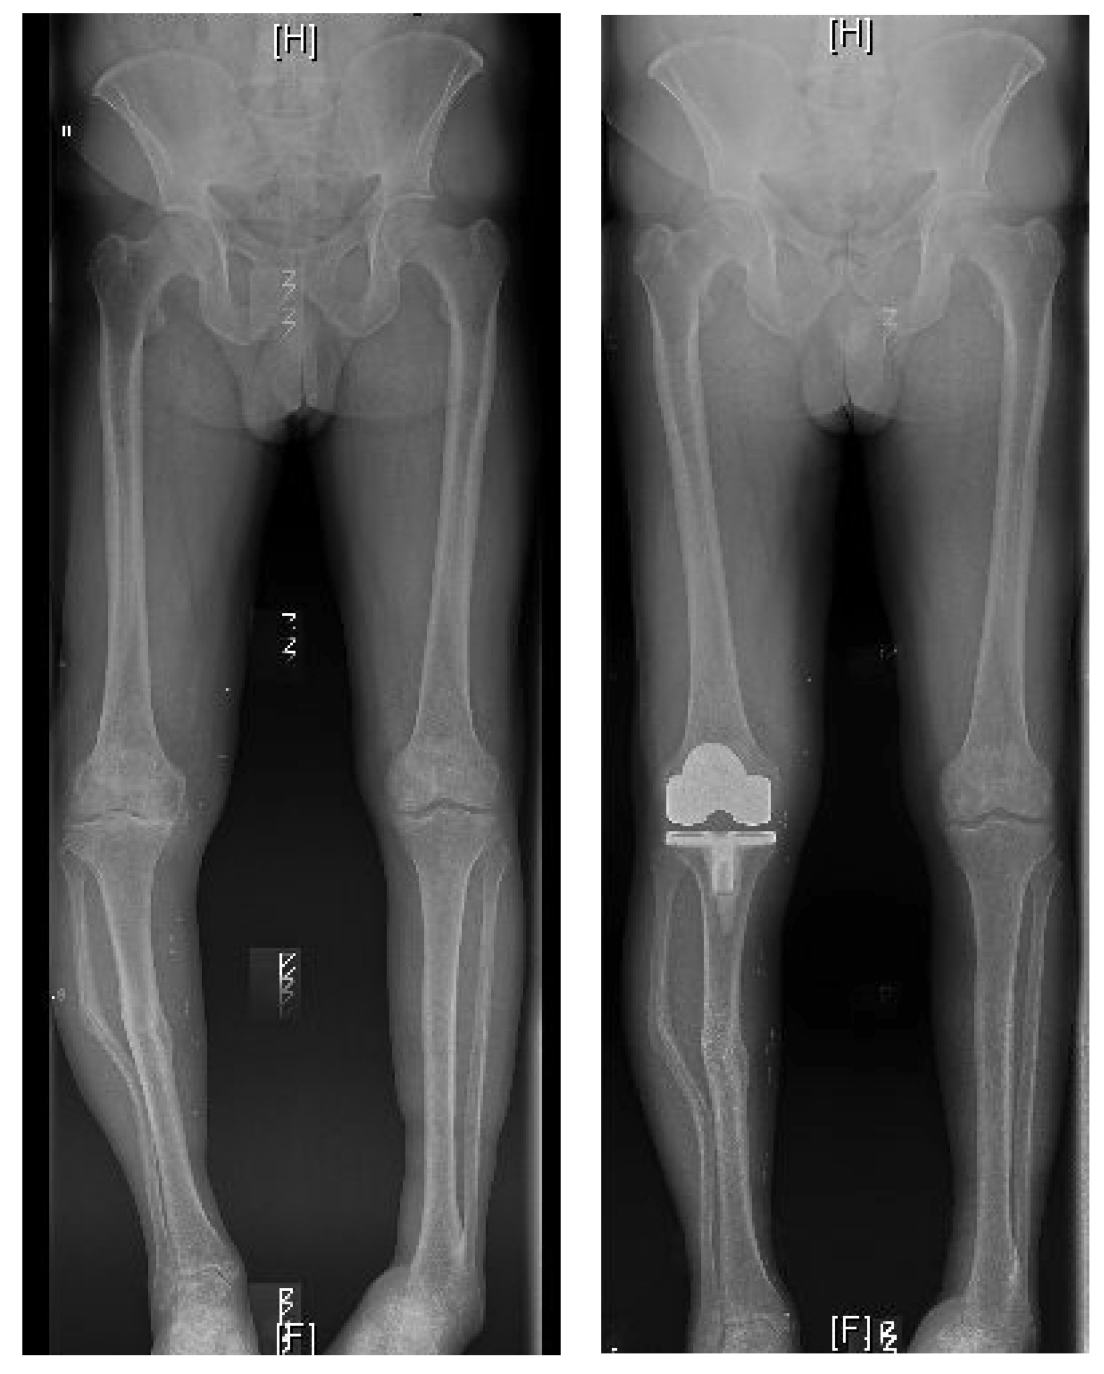

BILATERAL HIP REPLACEMENT

"Getting my life back"

I'm so trilled with my new hips I thought I'd email you to fill you in on what they are doing for me: Climbed a gate with ease about 2 weeks ago, something I haven't been able to do for a few years. Did a 16km canal walk last week with ease and even better no grumbling legs/joints afterwards

TOTAL HIP REPLACEMENT

"Incredible experience improving my life"

Mr. Vioreanu is an incredible surgeon who significantly improved my mobility and quality of life in just 2 days after hip replacement surgery!

"Thoroughly Professional Care"

I had my hip replaced with Mr. Vioreanu last year. I was suffering for years with my hip but it was only afterwards I realised how much pain and discomfort I was living with. From the first time I met Mihai I felt comfortable with the man who eventually would be operating on me. He explains things in a manner that even a novice like myself can understand.

"Walking poles only two weeks after surgery - I am so happy"

As a woman in her sixties, who has always been active, I was delighted to be introduced to Mr Vioreanu. A friend had recommended me to him as her GP was impressed with her rapid recovery. At the consultation the information was clear and I was given a very informative booklet to take away and study. I was admitted on a Tuesday morning, operated on Tuesday afternoon and home on Thursday evening.

"Very down to earth & Accessible at all times"

I attended the Beacon Hospital for almost nine years and the Hip and Knee Specialist was trying to bring my right knee 'back from the brink' with daily pain killers and injections. I decided to go attend Mr. Mihai Vioreanu and I liked him instantly. He told me that my right hip was causing most of my knee problems. I accepted what he said and had a Total Hip Replacement in April 2018. Life has been great since as I no longer take pain killers and I have no pain in my knee.

"Nothing was ever too much bother, whatever the request"

To all the staff at Sports Surgery Clinic. Just 6 weeks ago I received a hip replacement at your clinic and would like to take a few moments to express my sincere gratitude for the care and attention I received during my stay. From the very first moment of making contact with the clinic through a telephone enquiry, to the stages that followed - the first consultation, checking in, my pre op consultation, until my discharge 3 days later;

"A New lease of Life totally pain free"

I would just like to thank Mr Vioreanu for the fantastic work which he performed on my hip which was really badly deteriorated and I was in agonising pain and discomfort to the point of struggling to walk. I attended his clinic and had a diagnosis and scan immediately, and successful surgery within two weeks.

" My Highest Recommendation "

A perfect schedule, excellent briefing, completely detailed. My recovery post discharge was rapid and I'm extremely grateful for choosing Mr. Mihai Vioreanu as my specialist.

"Dr. Vioreanu went out of his way for me"

Dr Vioreanu really went out of his way for me and after only 2 weeks I was having the surgery. I couldn't  believe how lucky I was. The surgery went very well and I could walk with no pain straight away after the operation.

Bilateral Revision Hip Replacement

" I can't express this clearly enough: you've come to the right surgeon! "

In my many decades' experience with hip operations Mihai Vioreanu has stood out for two reasons: the exceptional skill he brings to his surgeries, and the depth of empathy, humanity and kindness he shows to his patients.